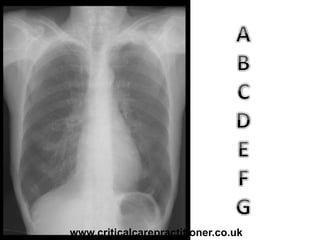

TECHNICALS

AIRWAY

BONES

cARDIAC

DIAPHRAGM

GASTRIC BUBBLE

EQUAL LUNG FIELDS

Rotation?

Penetration?